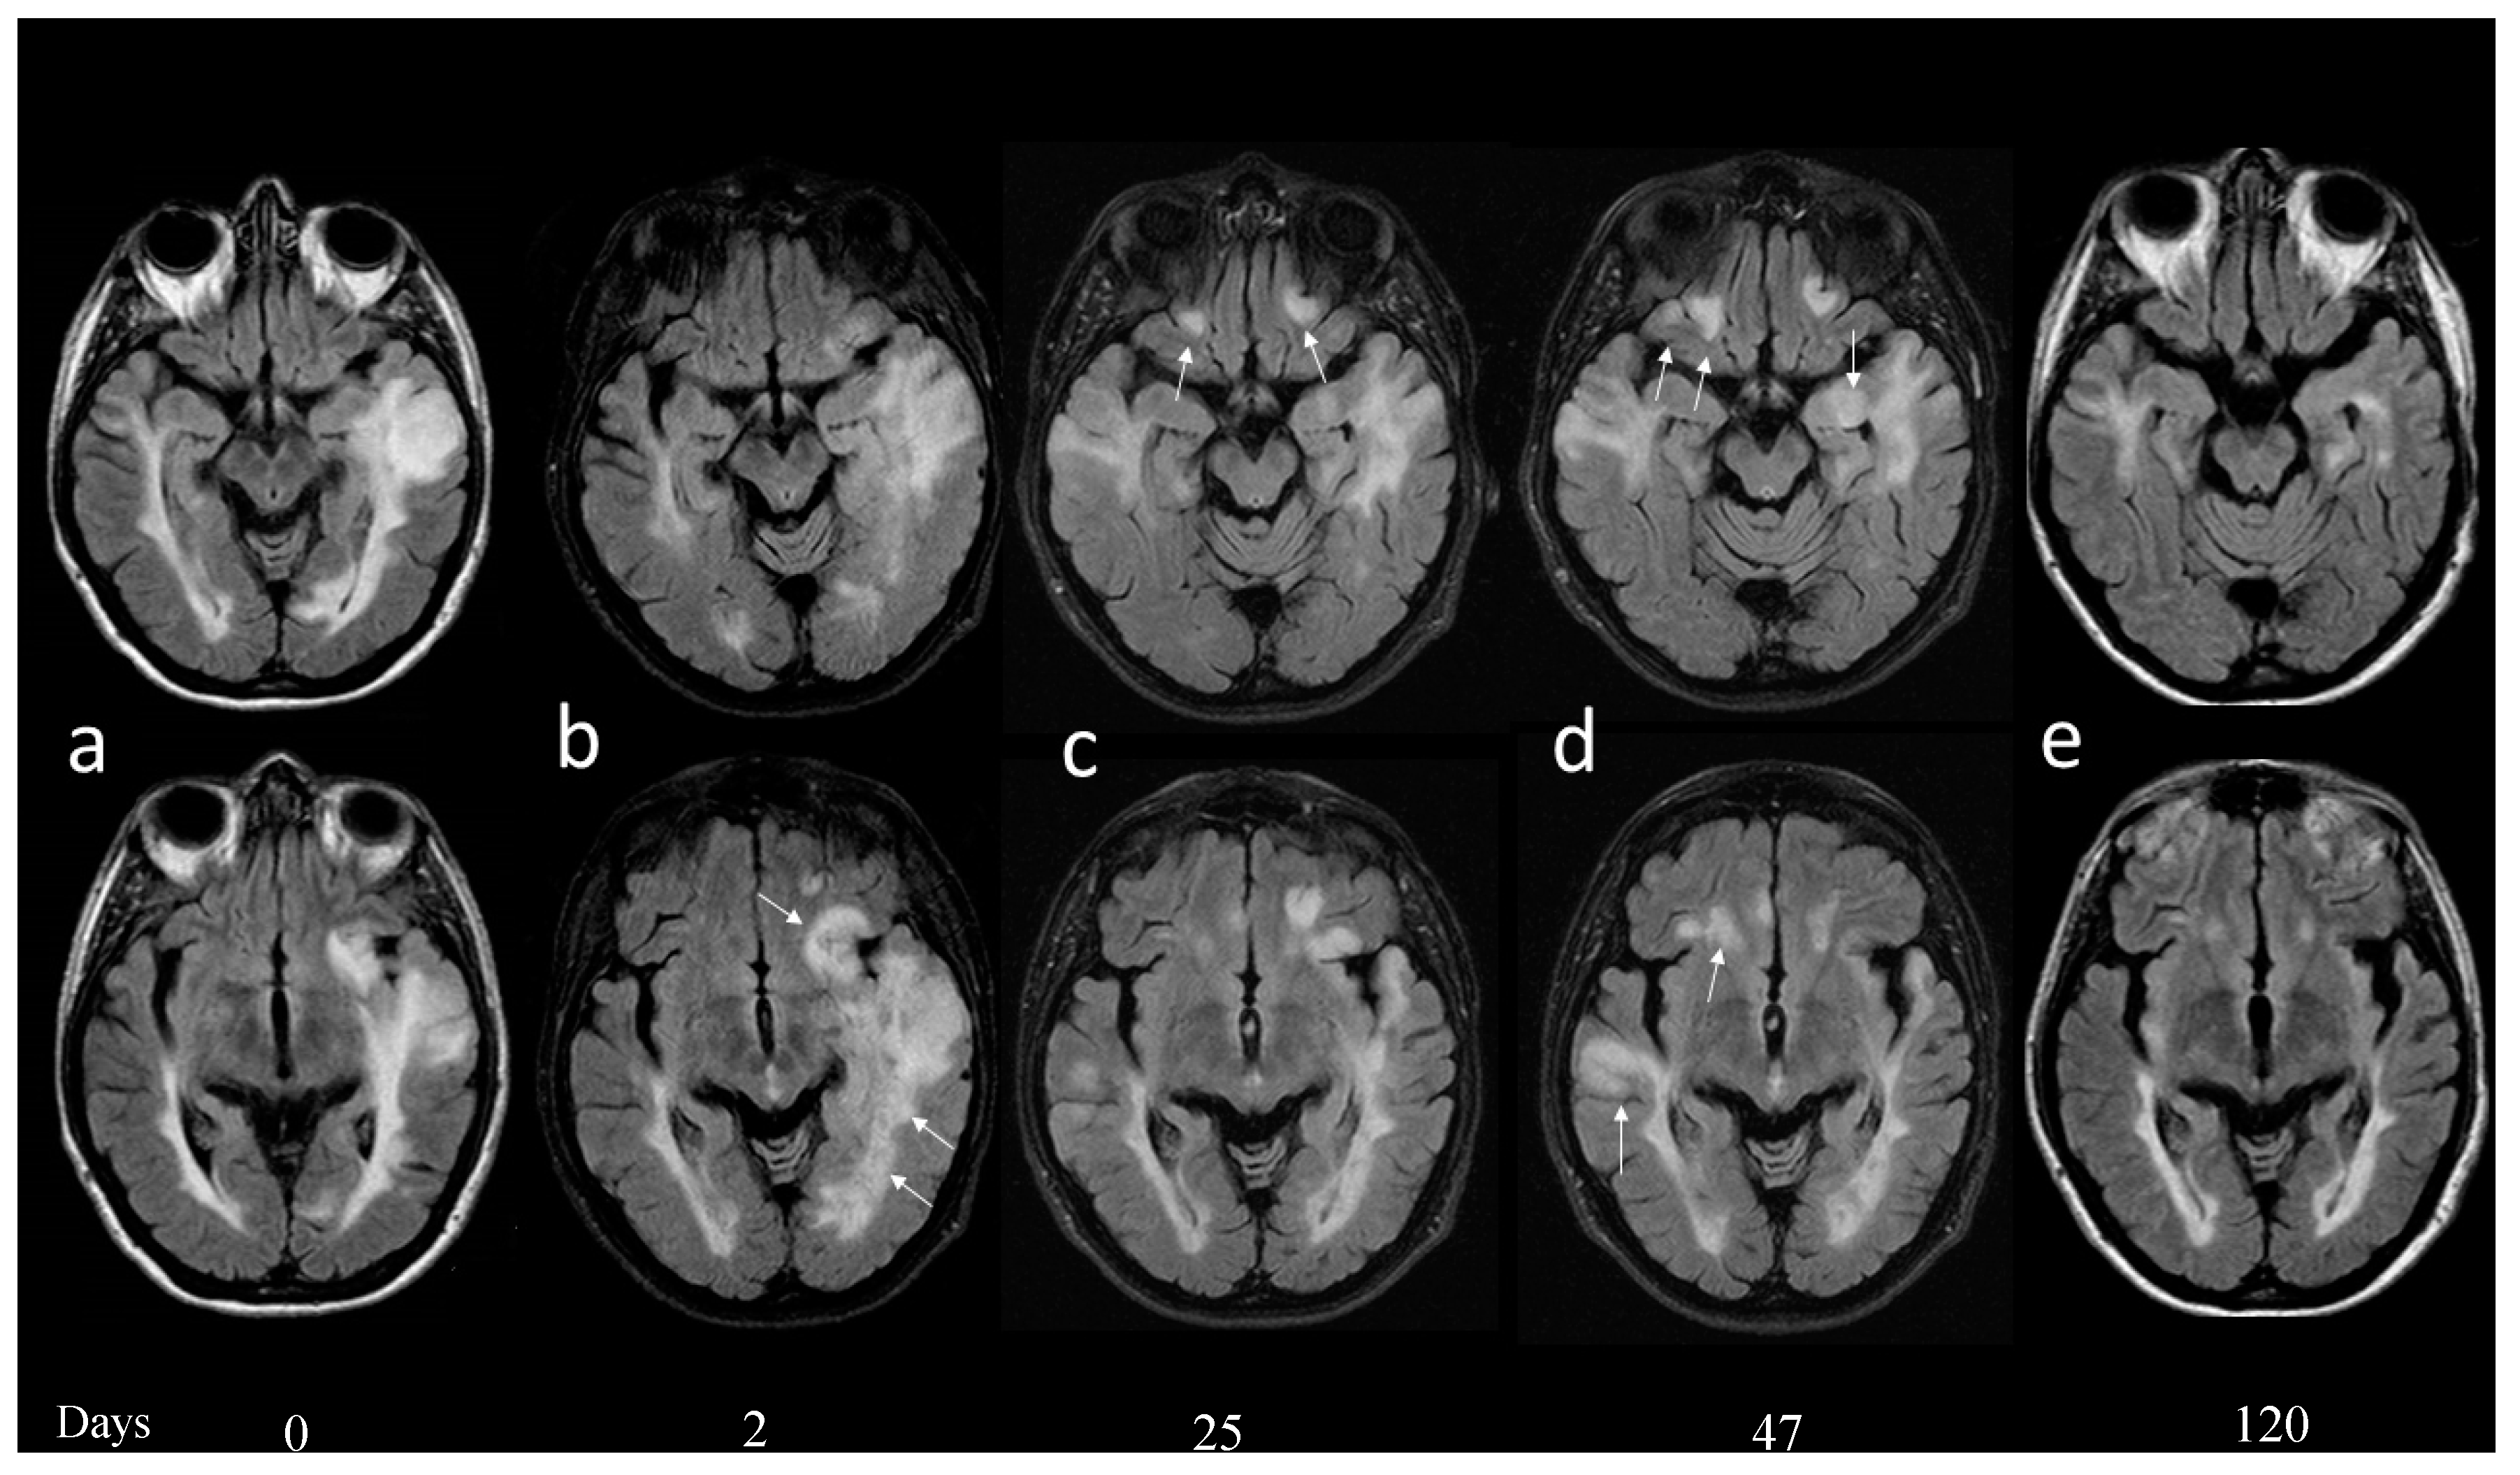

Autoimmune Encephalitis and CSF Anti-GluR3 Antibodies in an MS Patient after Alemtuzumab Treatment

2. Case Report